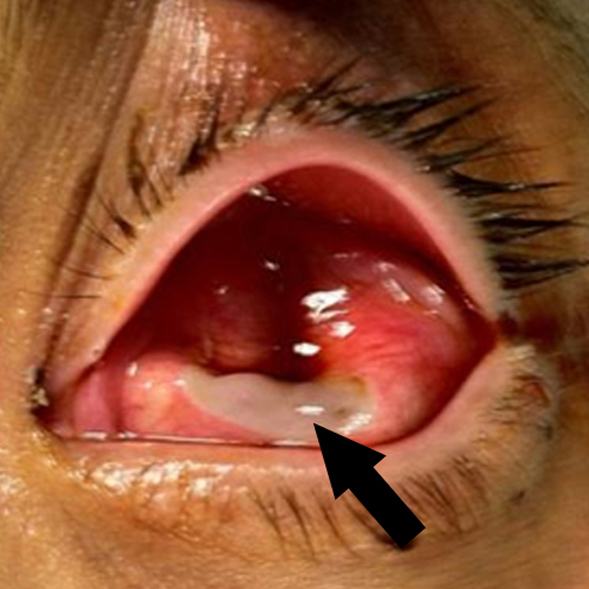

Clostridium septicum endophalmitis associated with colon adenocarcinoma

Jacob L. Eisenrich, BS, Angela M. Herro, MD, Mason Schmutz, MD, Kundandeep S. Nagi, MD